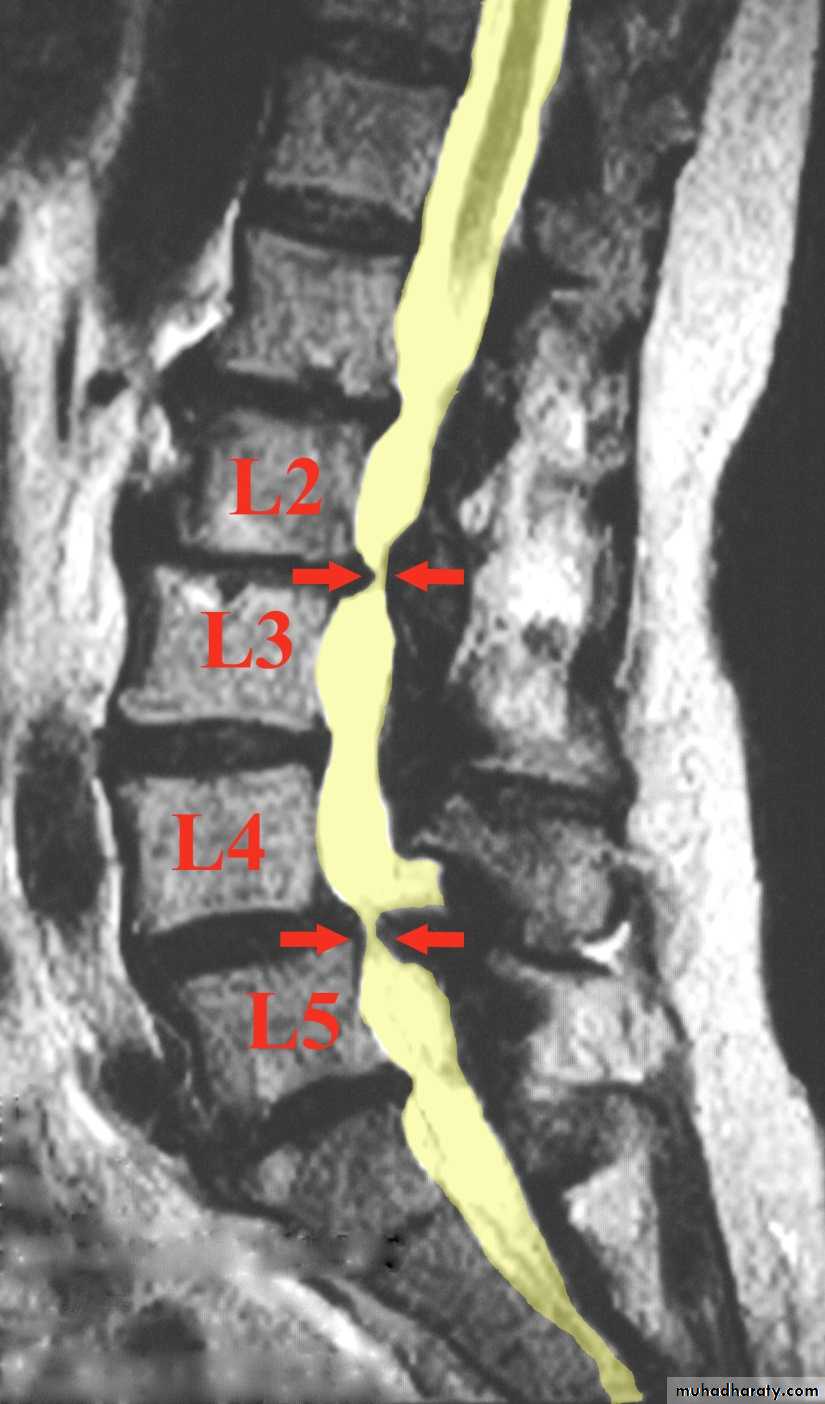

SPINAL STENOSIS

Abnormal narrowing of the central canal, the lateral recesses, or the intervertebral foramina to the point where the neural elements are compromised and the patient develops neurological symptoms and signs in the lower limbs.SPINAL STENOSIS

Two measurements are used: the mid-sagittal (anteroposterior) diameter and the inter-pedicular (transverse) diameter of the spinal canal. Normally, the diameters are 15 mm for the anteroposterior and 20 mm for the transverse. Anything less than 11 mm for the anteroposterior diameter and 16 mm for the transverse diameter is considered abnormal.

Imaging:X-rays will show features of disc degeneration or spondylolisthesis. Measurement of the spinal canal can be carried out on CT and MRI.